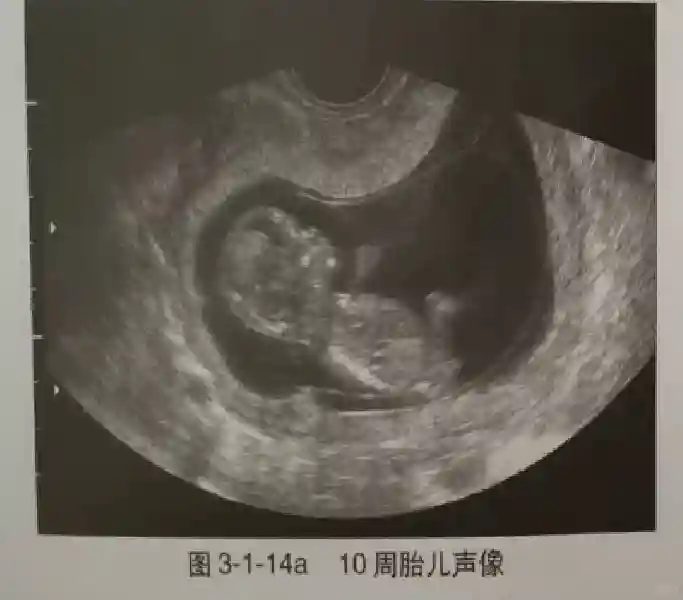

早孕早期建议采用阴道超声检查,以便早期了解胚胎发育情况,发现异常妊娠。早孕期超声是指从证实宫内妊娠到妊娠13+6周期间超声观察妊娠的情况,10周以前为胚胎,10周后为胎儿。

3??胚胎:胚胎通常在6-7周时可以为超声显示,起初为胎芽,表现为卵黄囊一侧局部组织增厚,达到1 -2 mm 时才有可能为超声测量出来。达4-5mm时可见胎心搏动,相应孕周为6-6.5周,妊娠囊大小为13-18mm。胚芽长度≥7㎜时仍未见心管搏动,提示胚胎停止发育。胚胎的出现和妊娠囊直径的关系:妊娠囊直径> 16 mm 时,经阴道超声应显示胚胎。妊娠囊直径> 25 mm 时,经腹超声均应显示胚胎。

4??胎心搏动:胎心搏动通常出现于6-6.5周,胚胎在4- 5mm就应该显示胎心搏动。